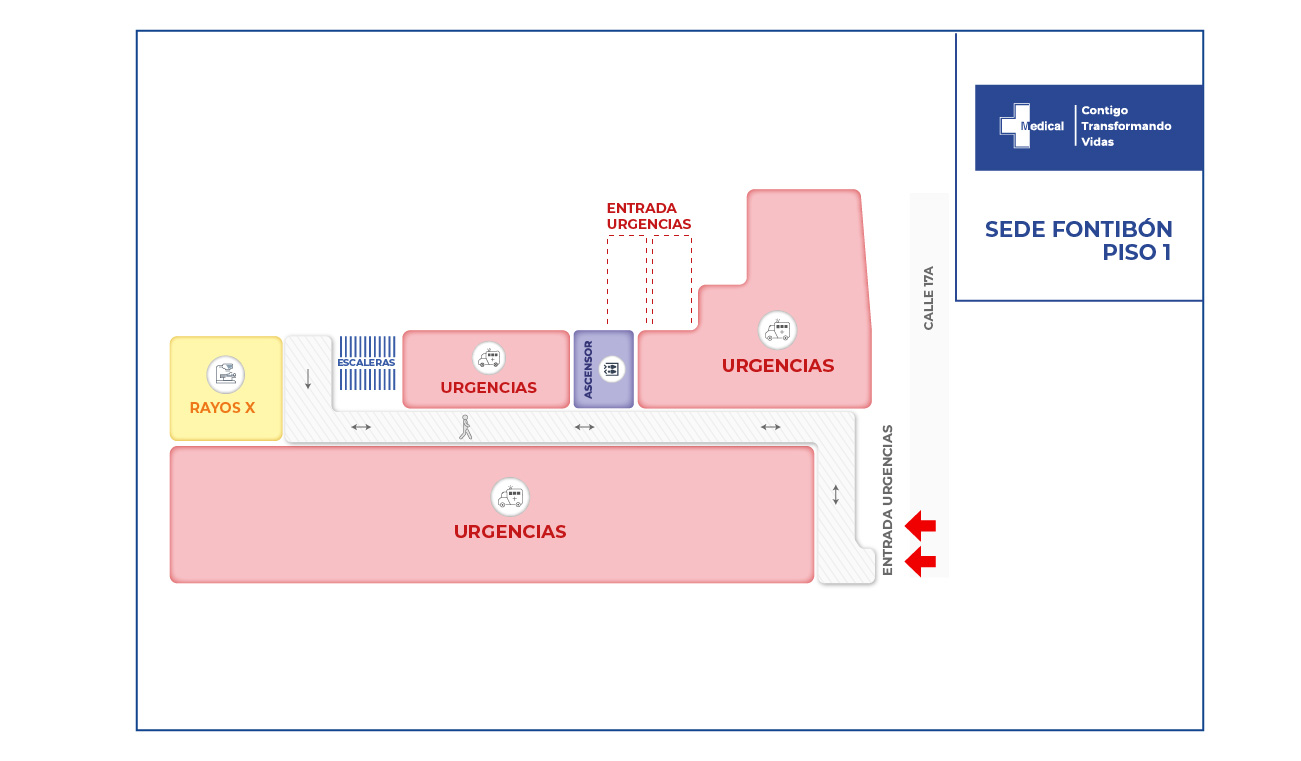

A nuestra institución ingresa paciente masculino de 28 años de edad, remitido de Saravena Arauca, quien sufrió accidente de alto impacto al conducir motocicleta.

Como consecuencia de este accidente presenta trauma craneoencefálico el cual produjo un hematoma subdural (acumulación de sangre entre la superficie y la capa más externa del cerebro), por otra parte presenta hemotórax bilateral ( sangrado entre la cavidad que recubre el pulmón y la pared torácica), cuenta con un trauma abdominal cerrado y por último el paciente tiene una fractura en la columna a nivel de las vértebras torácicas (T5-T6) las cuales se encargan de dar soporte y estabilidad en la columna; dicha fractura muestra una sección medular completa lo que indica que el paciente llega a nuestra institución parapléjico ( imposibilidad de mover las extremidades inferiores, con pérdida de sensibilidad y pérdida de control de esfínteres). Se trata de una paciente con un trauma mayor, con compromiso de su estabilidad hemodinámica que cuenta con alta probabilidad de fallecer.

La condición de ingreso es realmente poco alentadora, sin embargo la oportunidad de los servicios, la eficiencia y eficacia que caracteriza a la clínica Medical SAS, ofrece al paciente y su familia todo un equipo interdisciplinario para la atención adecuada y secuencial para este tipo de traumas. Precedida por especialistas en cirugía general, neurocirugía, psicología, psiquiatría, servicios de apoyo terapéutico y radiológico, salas de cirugía, unidad de cuidados intensivos, rehabilitación física, clínica de heridas, entre otros.